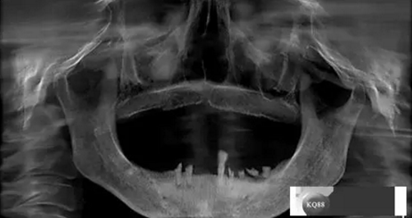

檢查:上頜無(wú)牙頜假牙穩(wěn)定性尚可,下頜3435364243殘根;33殘冠1-2度松動(dòng),其他牙齒缺失;CBCT檢查:下頜牙槽骨前牙區(qū)骨高度足,后牙區(qū)骨高度最低為8mm,骨寬度足。

1)術(shù)前檢查,拍攝臨床照片及CBCT檢查,制取活動(dòng)義齒參考模型,指導(dǎo)后期最終修復(fù)的牙齒排列